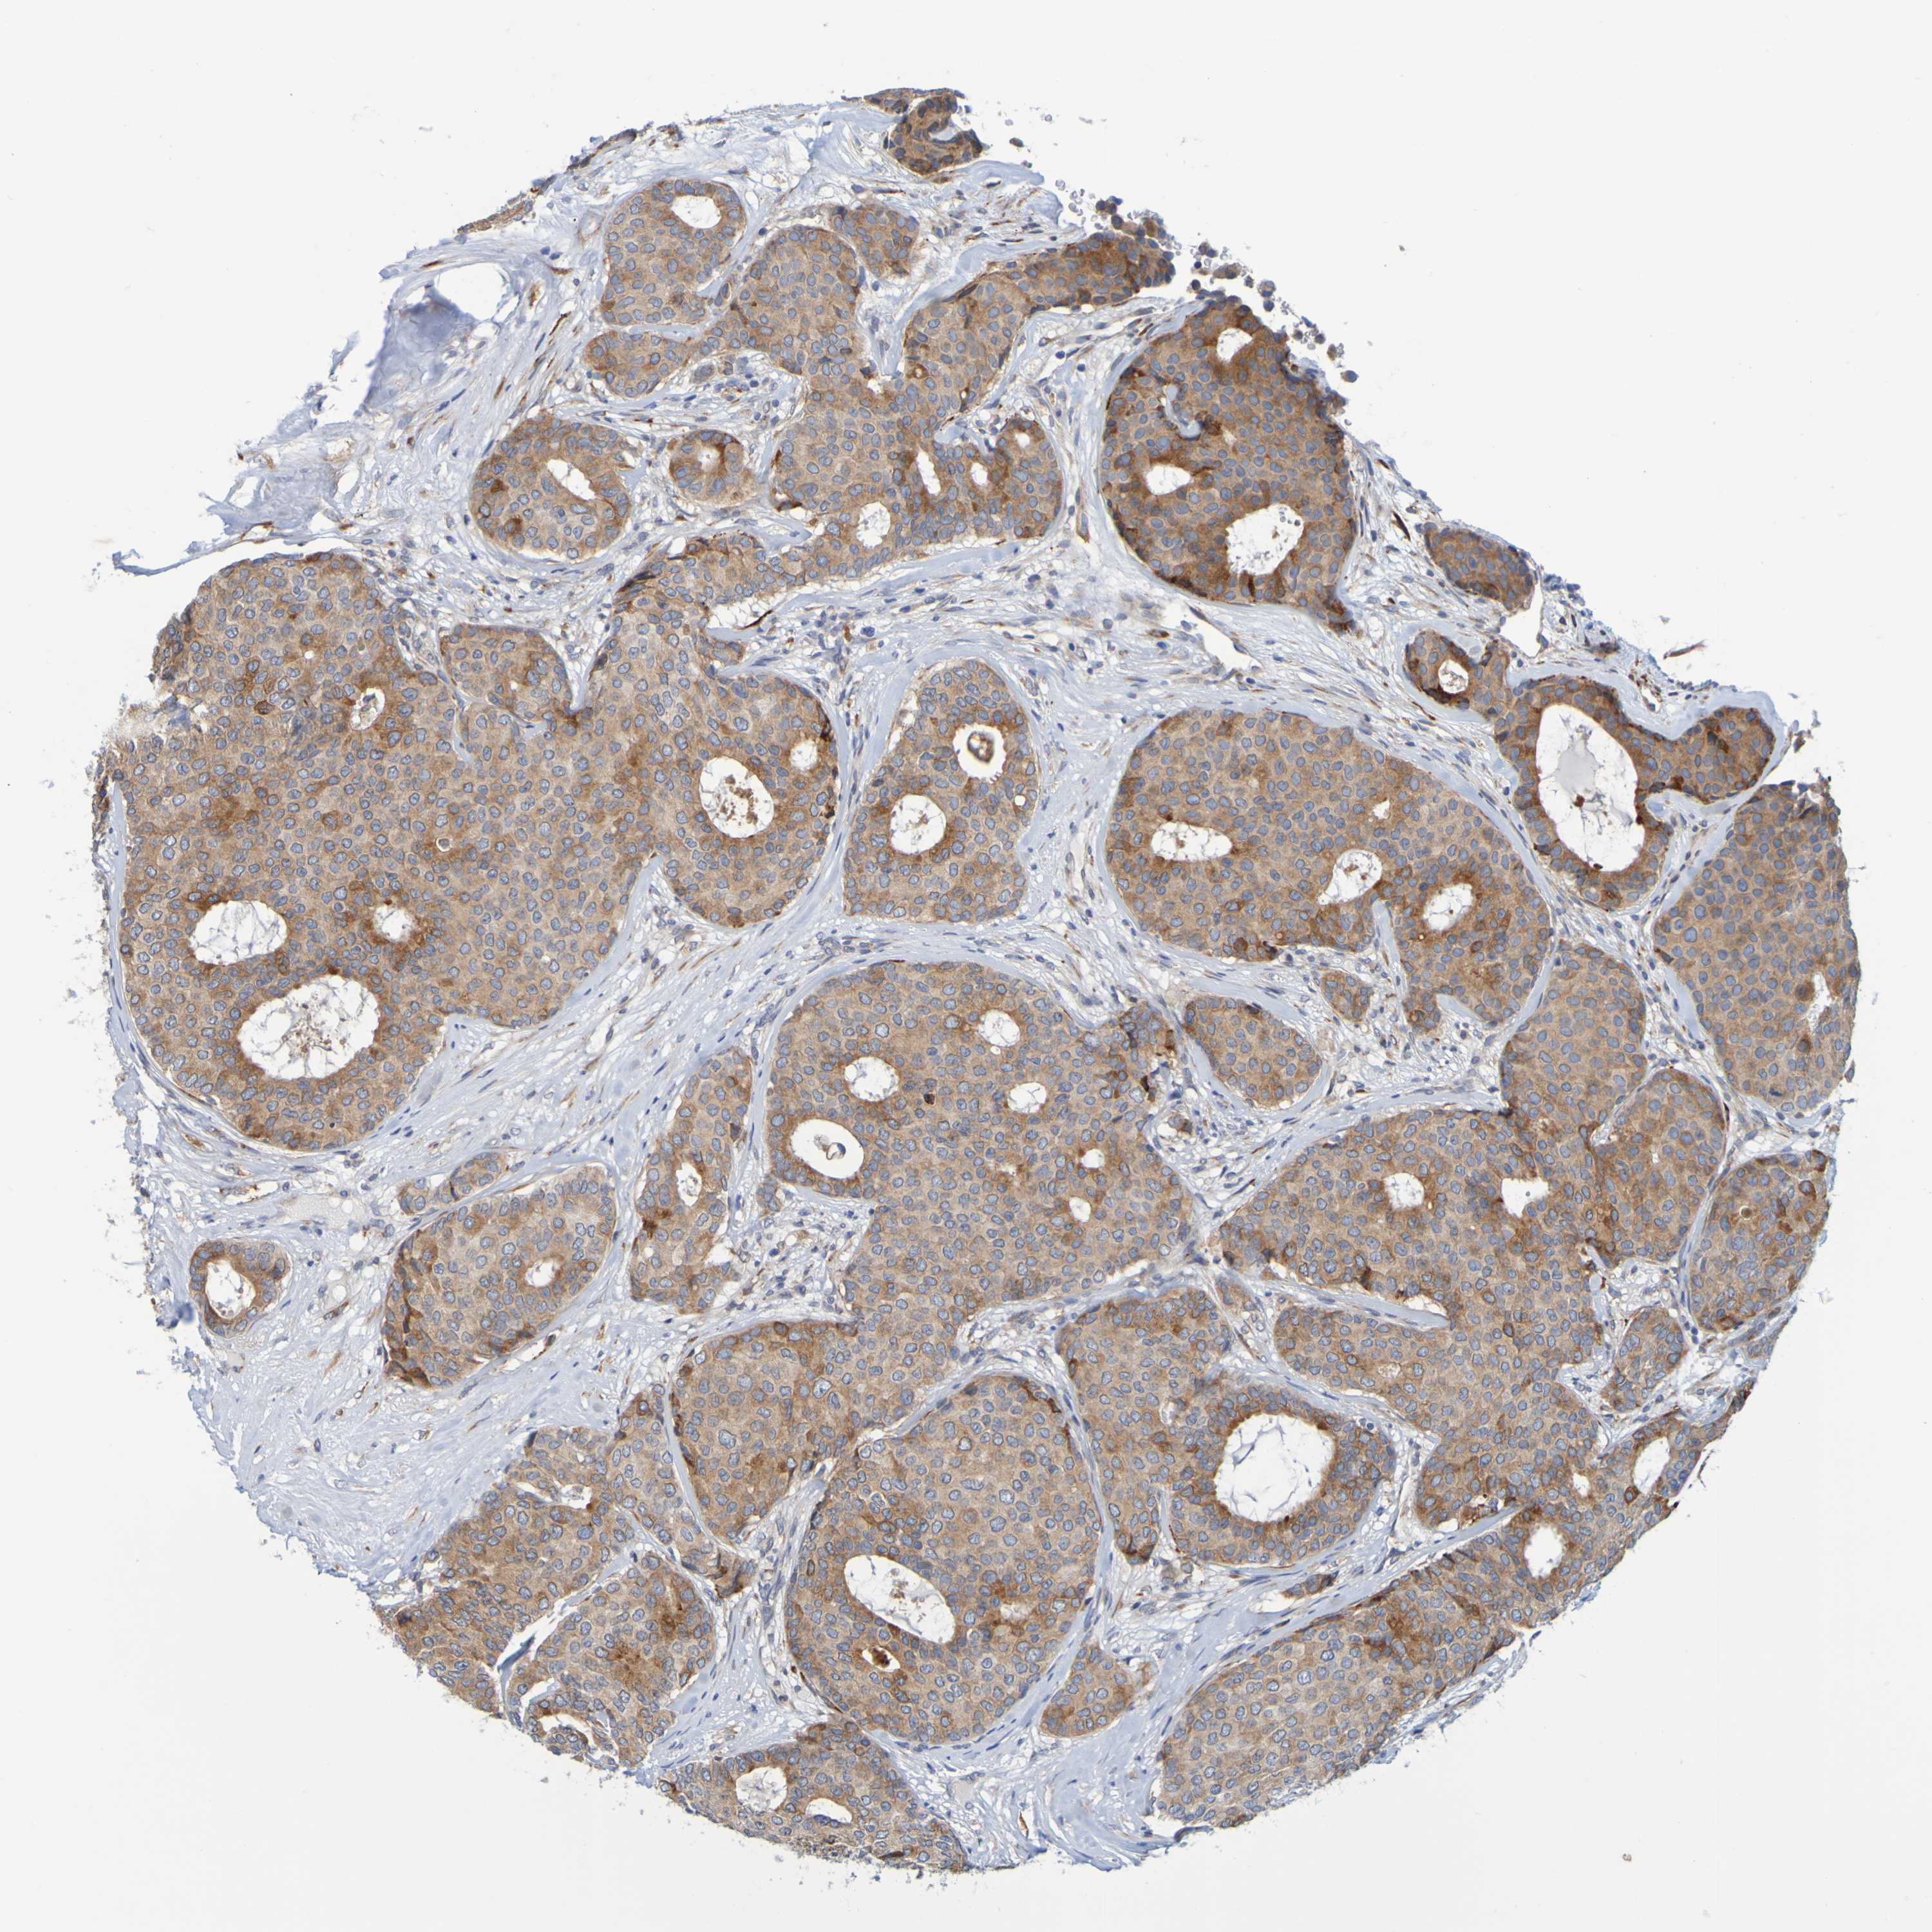

CANCER BREAST CANCER Show tissue menu

BRCA TCGA BRCA VALIDATION PROTEIN EXPRESSION